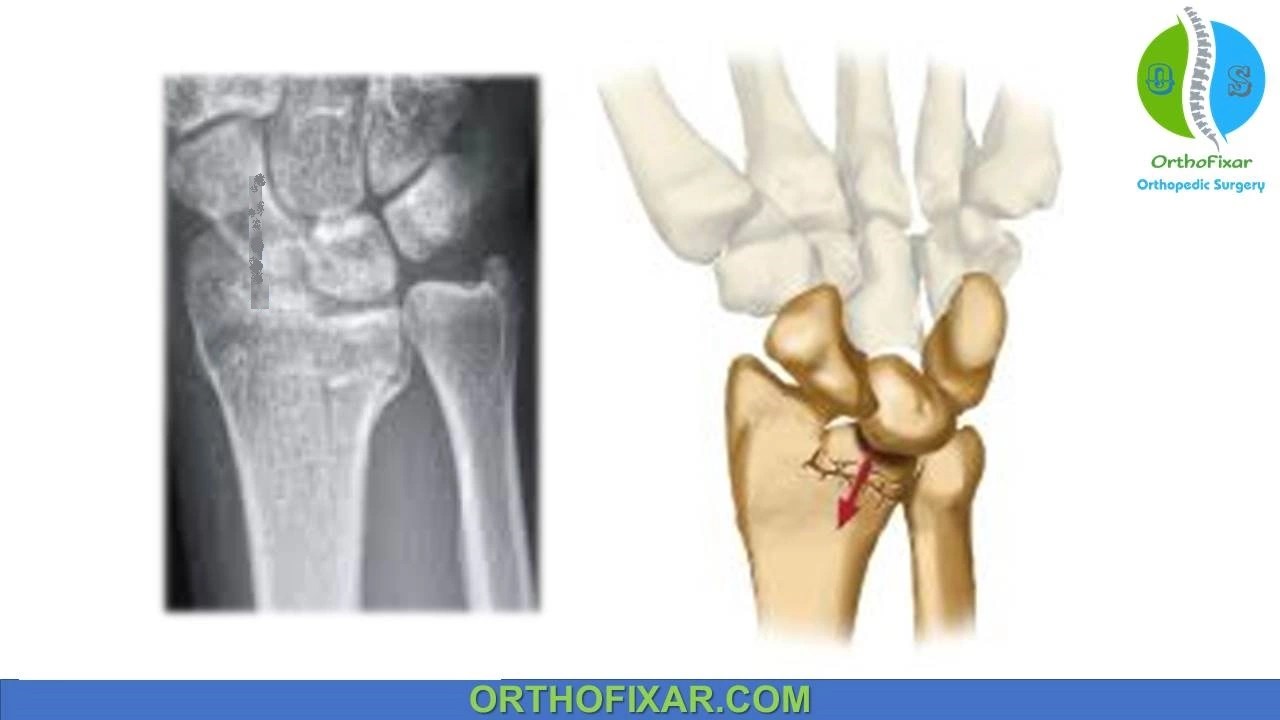

Die Punch Fracture Distal Radius

Distal radius diepunch fracture Image Die Punch Fracture Orthobullets Arthroscopic reduction of dorsal barton’s fracture offers an alternative that limits exposure of the dorsal carpus and that may help maintain blood supply to the dorsal fracture components. Isolated dr fractures typically include smith’s, colle’s, torus/buckle,. Retract fcr tendon ulnarly and incise through the dorsal aspect of the fcr sheath can retract fcr radially if carpal tunnel access is. It. Die Punch Fracture Orthobullets.

Singlecolumn diepunch fracture. (A) Sketch of a single column Die Punch Fracture Orthobullets It is by definition depressed or impacted and is named. Arthroscopic reduction of dorsal barton’s fracture offers an alternative that limits exposure of the dorsal carpus and that may help maintain blood supply to the dorsal fracture components. Confirm plate placement and fracture reduction with fluoroscopy secure the plate to the distal fragment using one or two cancellous. Retract fcr. Die Punch Fracture Orthobullets.